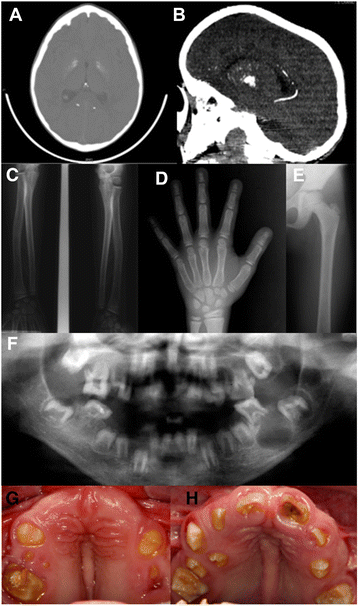

Background: Raine syndrome (RS) is a rare autosomal recessive bone dysplasia typified by osteosclerosis and dysmorphic facies due to FAM20C mutations. Initially reported as lethal in infancy, survival is possible into adulthood. We describe the molecular analysis and clinical phenotypes of five individuals from two consanguineous Brazilian families with attenuated Raine Syndrome with previously unreported features.

Results: Family 1 included 3 siblings with hypoplastic Amelogenesis Imperfecta (AI) (inherited abnormal dental enamel formation). Mild facial dysmorphism was noted in the absence of other obvious skeletal or growth abnormalities. A mild hypophosphataemia and soft tissue ectopic mineralization were present. A homozygous FAM20C donor splice site mutation (c.784 + 5 g > c) was identified which led to abnormal cDNA sequence. Family 2 included 2 siblings with hypoplastic AI and tooth dentine abnormalities as part of a more obvious syndrome with facial dysmorphism. There was hypophosphataemia, soft tissue ectopic mineralization, but no osteosclerosis. A homozygous missense mutation in FAM20C (c.1487C > T; p.P496L) was identified.

Conclusions: The clinical phenotype of non-lethal Raine Syndrome is more variable, including between affected siblings, than previously described and an adverse impact on bone growth and health may not be a prominent feature. By contrast, a profound failure of dental enamel formation leading to a distinctive hypoplastic AI in all teeth should alert clinicians to the possibility of FAM20C mutations.